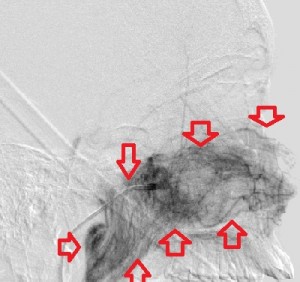

Fourth panel, left to right: Digital subtraction angiogram of the left internal maxillary artery before (1st two images, a frontal and a lateral view of the face) and after embolization (the last image, a lateral view). (For the 2nd and 3rd images, assume the patient’s face is turned to your right). Note the intense blushing of the tumor before embolization emphasizing its vascularity. Following embolization the mass is invisible.

Severel treatment options for JNA have been described in the literature, some now obsolete. They include hormonal therapy (the tumor has receptors for many male hormones), radiation, embolization, chemotherapy, open surgical removal, and, in the last 2 decades, endoscopic resection of the mass. Hormonal therapy is largely abandoned for its ineffectiveness. Radiotherapy has been applied as definitive treatment for advanced JAN and has local control rates between 85% and 91%. However, it may be complicated by panhypopituitarism, growth retardation, cataracts, radiation keratopathy, temporal lobe necrosis, and malignant transformation of the tumor, especially with high doses of radiation. It is perhaps excellent in treating primary or recurrent disease in critical areas, where surgical excision of the tumor may be hazardous. Open surgical extirpation was the only method of resecting the disease before the advent of modern novel techniques like endoscopic resection and radiofrequency coblation. There are many approaches to resecting the disease each dependent on the location and extent of the tumor. It is sometimes combined with endoscopic resection. Bland embolization of JNA is ususally offered as a presurgical intervention to limit hemorrhage during surgical removal. The usual arterial source to the tumor is the internal maxillary artery, but it may receive branches from the ophthalmic artery, ascending pharyngeal artery, and the facial artery. Identifying and embolizing these sources reduces the amount of intra-operative blood loss by 50% or more and creates a relatively bloodless operating field that improves tumor resection. When embolization is offered, surgical resection should be done in 2 to 5 days to avoid the development of collateral supply to the tumor. Endoscopic resection of the tumor enjoys certain advantages over traditional open surgery: comesis (no facial scars), shorter hospital stay that translates to lower cost; shorter recuperation; and better or equal recurrence rate. However, there are controversies over what stage of the disease is best treated by this technique. (I have eliminated the staging of JAN in this writing for want of space.)